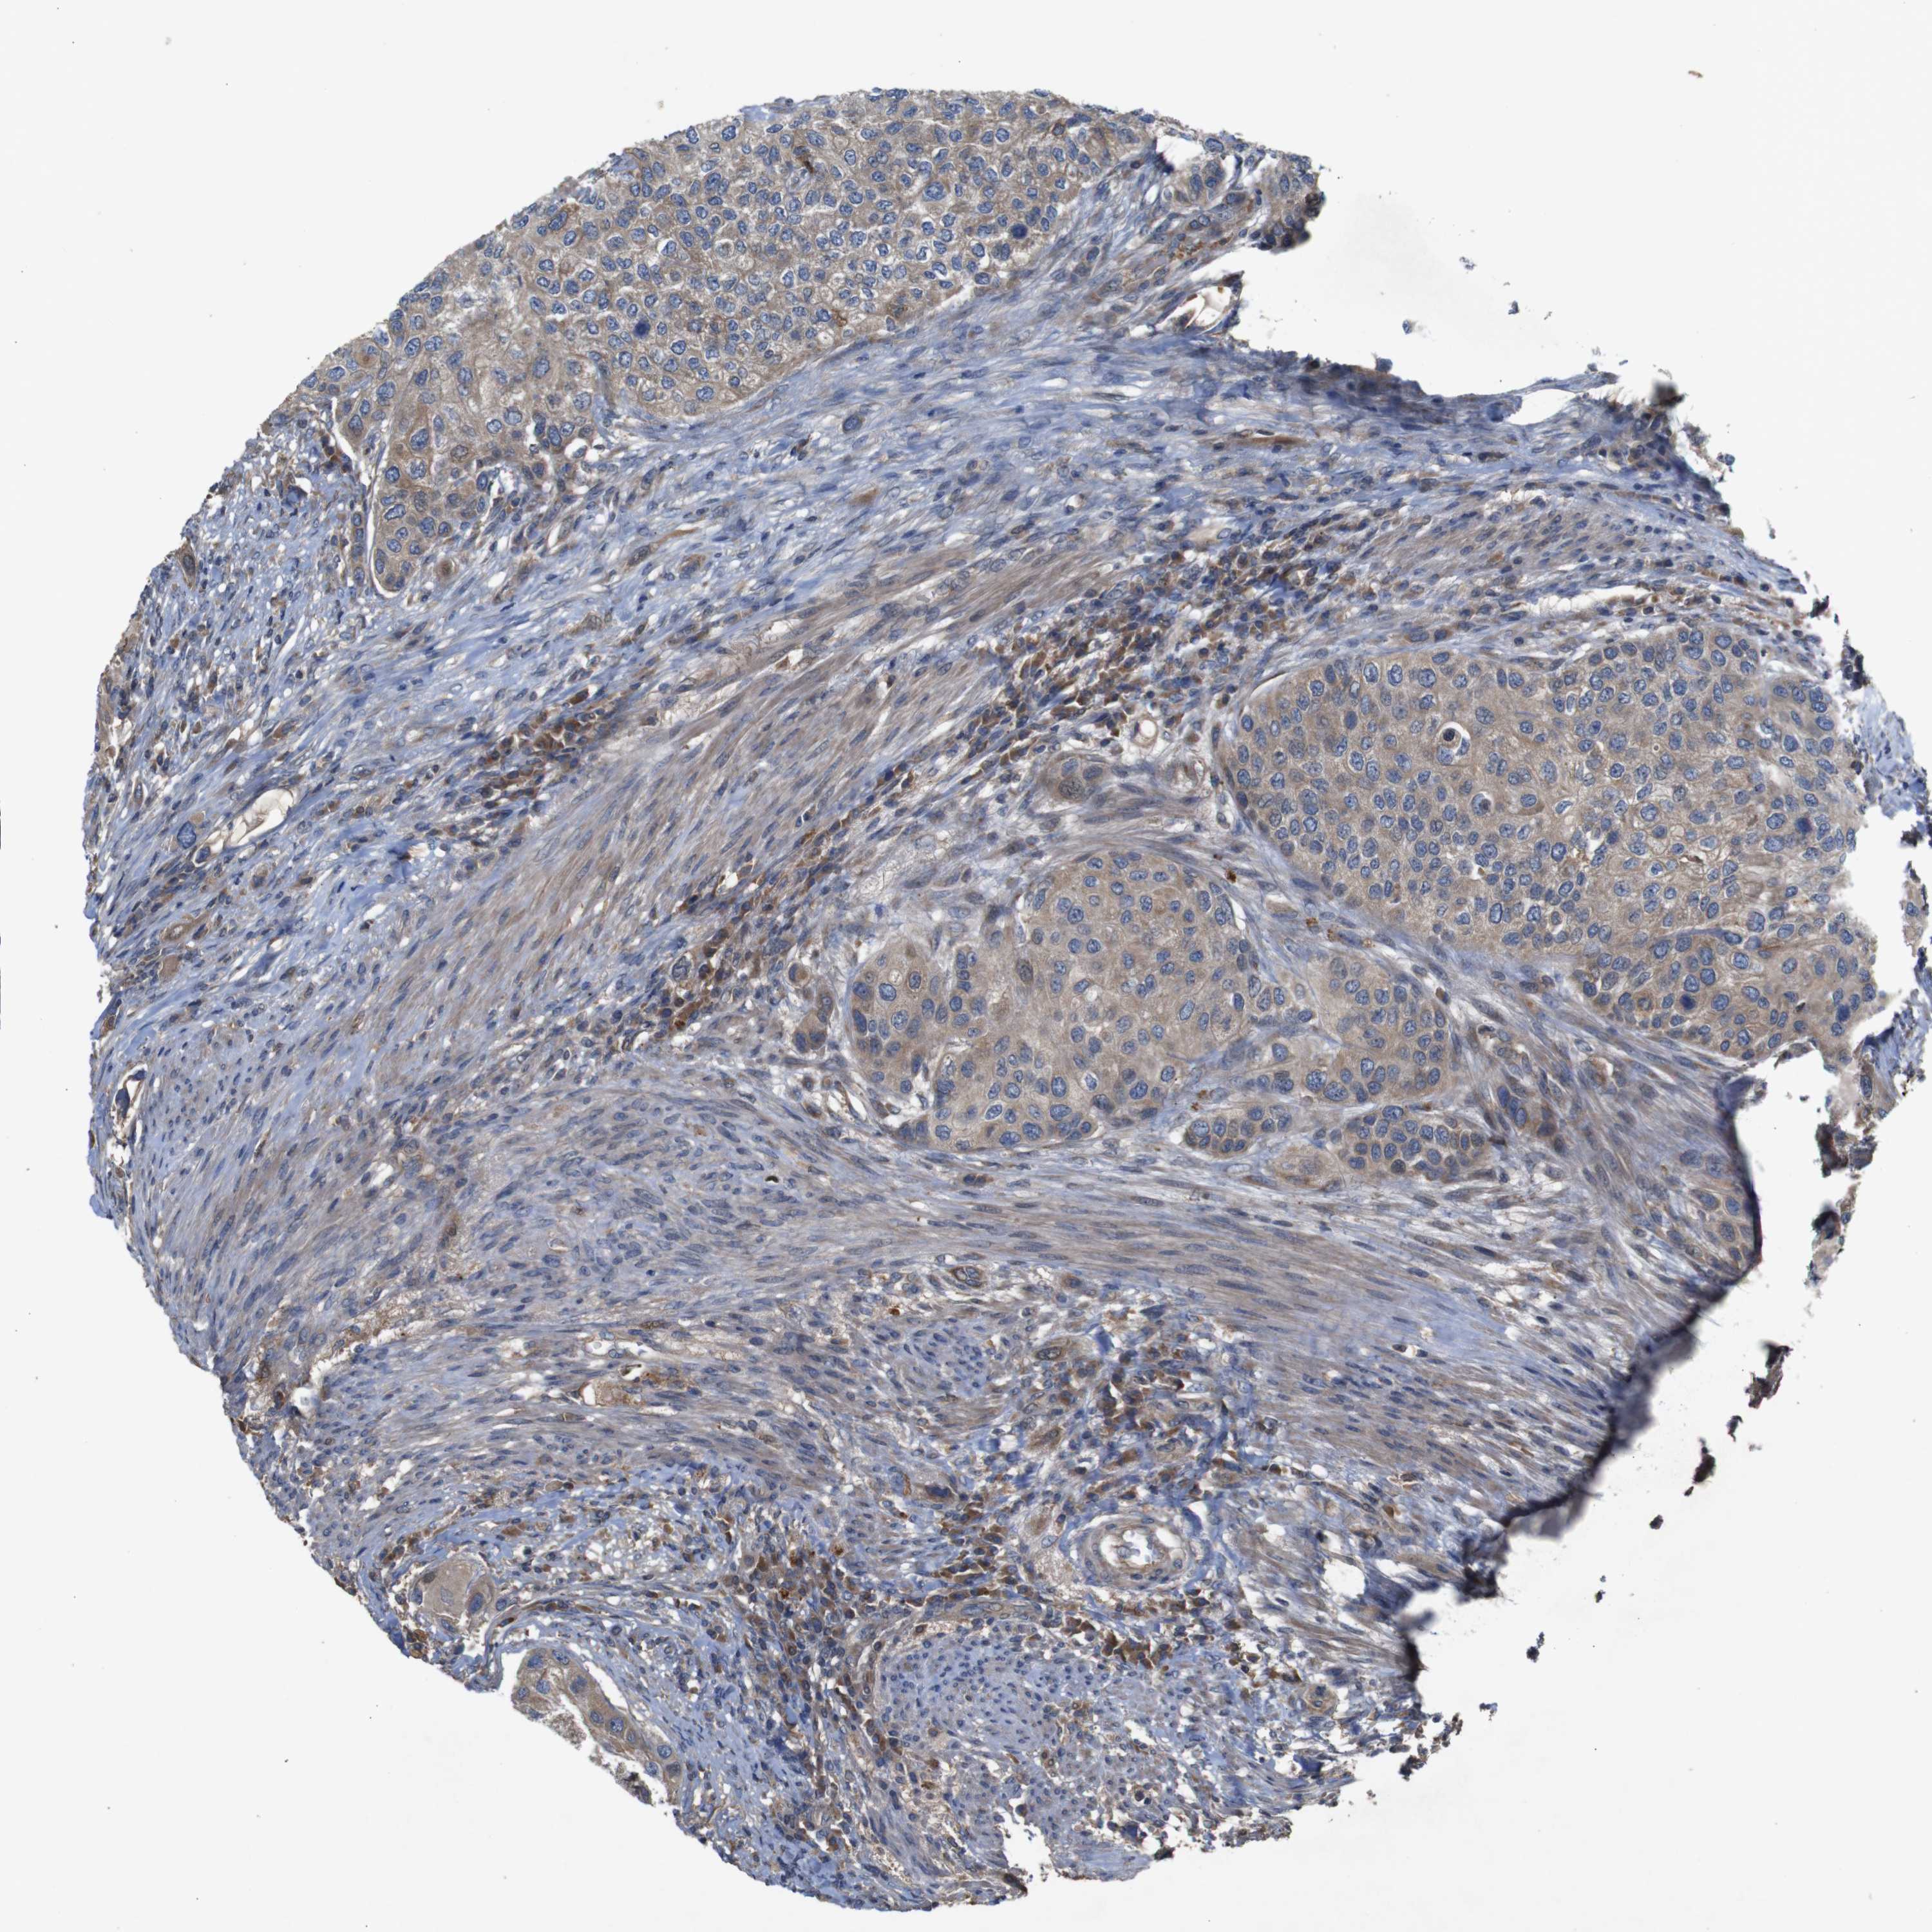

UROTHELIAL CANCER - Protein expressioni

A mouse-over function shows sample information and annotation data. Click on an image to view it in a full screen mode. Samples can be filtered based on level of antibody staining by selecting one or several of the following categories: high, medium, low and not detected. The assay and annotation is described here.

Note that samples used for immunohistochemistry by the Human Protein Atlas do not correspond to samples in the TCGA dataset.

Antibody stainingi

Antibody staining in the annotated cell types in the current human tissue is reported as not detected, low, medium, or high, based on conventional immunohistochemistry profiling in selected tissues. This score is based on the combination of the staining intensity and fraction of stained cells.

Each image is clickable and will lead to virtual microscopy that enables deeper exploration of all samples and also displays staining intensity scores, fraction scores and subcellular localization as well as patient and tissue information for each sample.

Antibody HPA012542

Antibody CAB009329

Antibody CAB015217

Staining

High

Medium

Low

Not detected

Intensity

Strong

Moderate

Weak

Negative

Quantity

>75%

75%-25%

<25%

None

Location

Nuclear

Cytoplasmic/membranous

Cytoplasmic/membranous,nuclear

Urothelial carcinoma, Low grade

Urothelial carcinoma, High grade